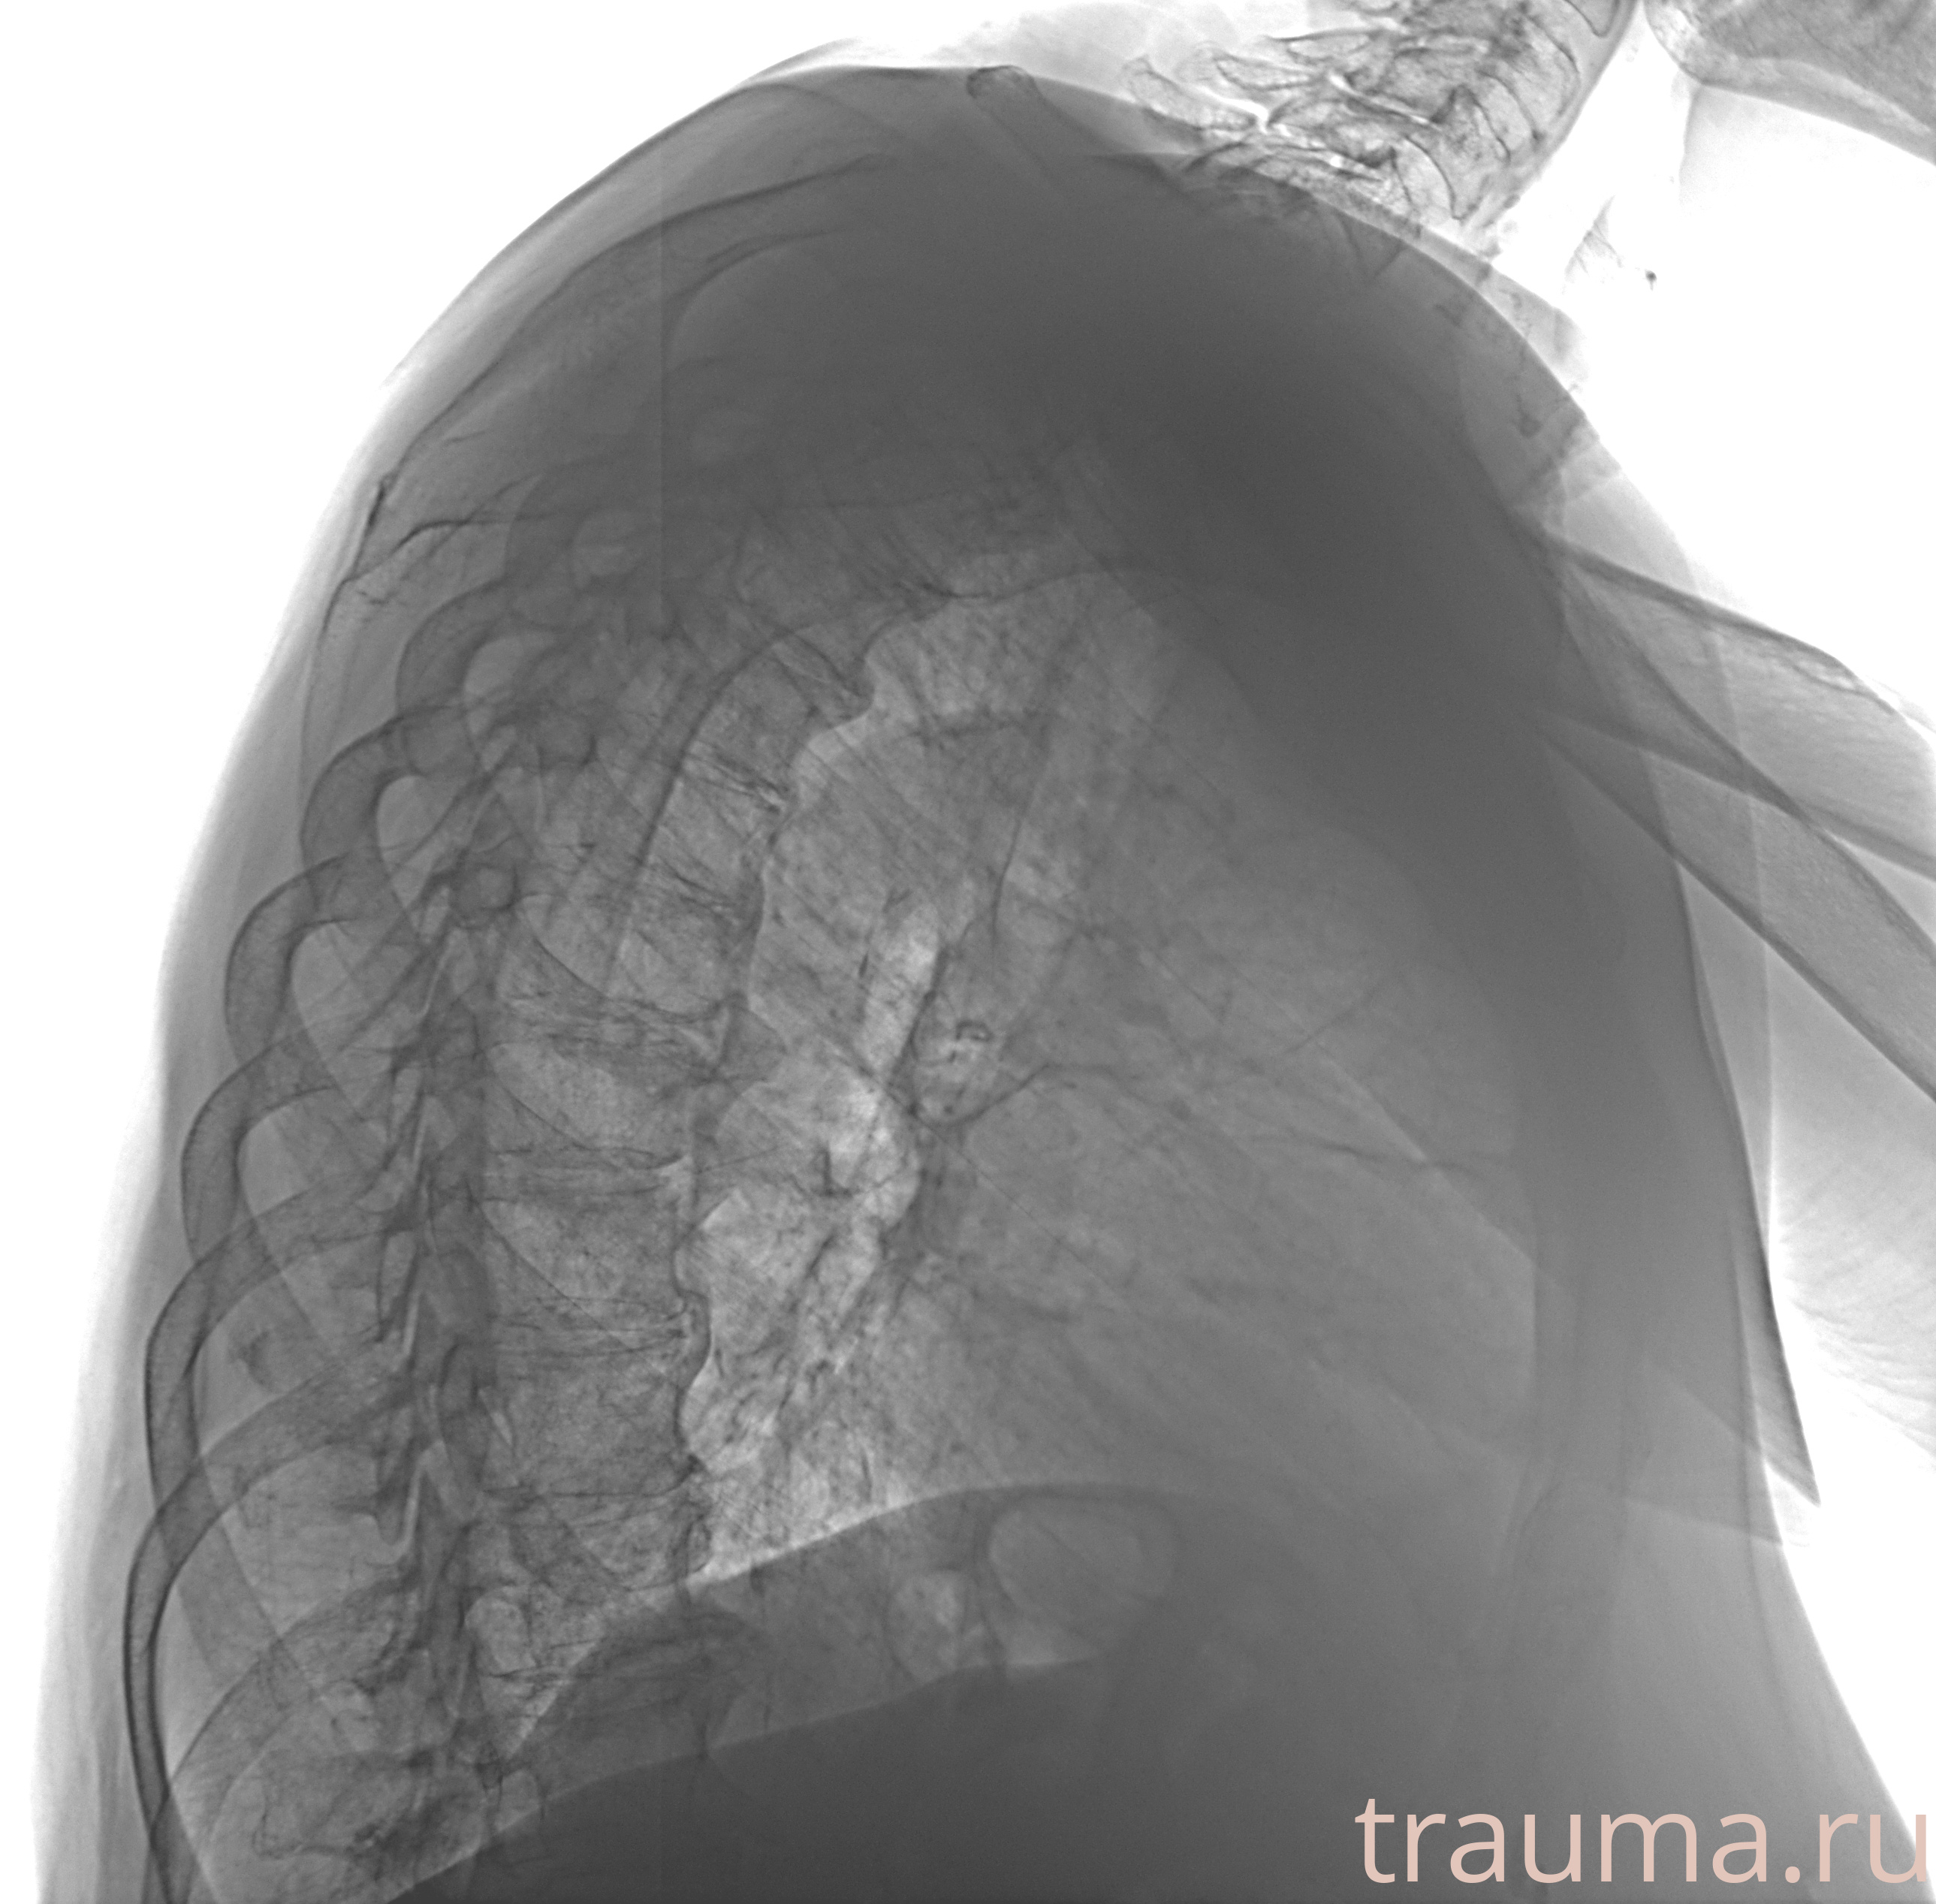

Рентген на дому: по вашему адресу приезжает врач-рентгенолог, травматолог-ортопед с мобильным рентгеновским аппаратом, проводит диагностику травмы или заболевания, делает необходимые рентгенограммы, дает рекомендации по дальнейшему лечению. Получить качественные снимки в домашних условиях возможно благодаря уникальной методике, разработанной МосРентген Центром для института  Склифосовского